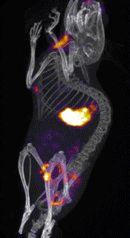

Small Animal Imaging Facility

The Small Animal Imaging Facility, part of the Advanced Imaging Laboratories, is located in the SVM vivarium of the Division of Laboratory Animal Medicine. The Small Animal Imaging Facility provides imaging support services for investigators, including

The goal of the Small Animal Imaging Facility is to provide state-of-the-art noninvasive imaging support to investigators who use small animal models in their research. The Small Animal Imaging Facility also welcomes users from other areas and interests who would like to use imaging in their research. We support investigators at LSU, as well as from outside institutions. We can also provide contact information for additional imaging resources in Baton Rouge and beyond.